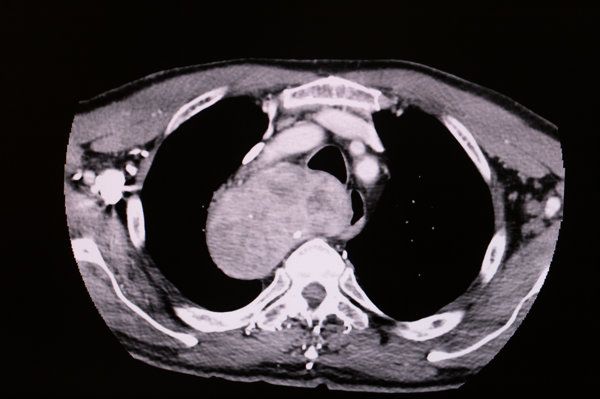

甲狀腺結(jié)節(jié)CT增強(qiáng)后不均強(qiáng)化可能表明結(jié)核病或其他疾病的存在。

結(jié)核病是一種由結(jié)核分枝桿菌引起的傳染病,其特征是受累器官的干酪樣壞死和滲出性病變。當(dāng)結(jié)核分枝桿菌侵犯甲狀腺時,會導(dǎo)致局部炎癥反應(yīng)和免疫細(xì)胞浸潤,進(jìn)而引發(fā)結(jié)核病灶。在CT增強(qiáng)掃描中,這些結(jié)核病灶因血管壁通透性的增加而出現(xiàn)強(qiáng)化,呈現(xiàn)出不均質(zhì)分布的特點。因此,甲狀腺結(jié)節(jié)CT增強(qiáng)后不均強(qiáng)化可能是結(jié)核病的表現(xiàn)之一,需要進(jìn)一步的檢查和診斷確認(rèn)。

此外,還應(yīng)考慮是否存在囊性變、出血或鈣化等伴隨征象,以輔助判斷結(jié)節(jié)性質(zhì)。

針對甲狀腺結(jié)節(jié)的影像學(xué)評估,應(yīng)綜合分析結(jié)節(jié)大小、形態(tài)、邊緣清晰度以及強(qiáng)化模式等信息,并結(jié)合臨床癥狀和其他實驗室檢查結(jié)果進(jìn)行綜合評估。